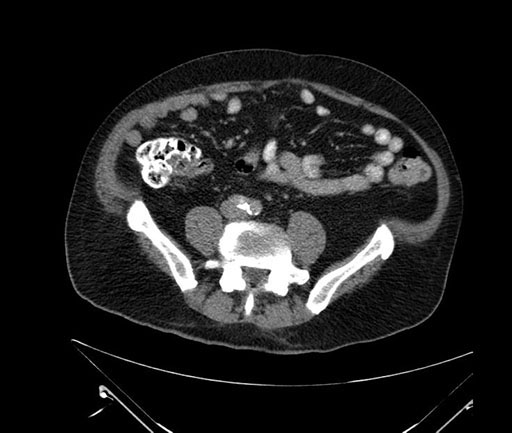

Imaging Analysis

Look through the patient's CT scan to identify any areas of concern for the necessary procedure.

Based on your CT findings, which issue(s) would give reason for "planned slowing down moment(s)" in this case?